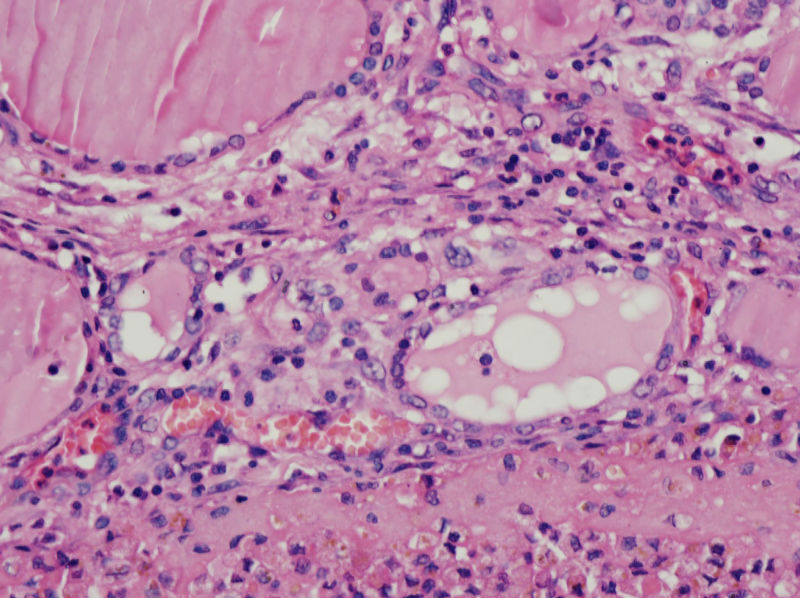

男,44,甲状腺囊肿.直径1.5公分,内流清亮液

请教老师们:有上皮内衬的一侧为囊壁的内衬上皮,是滤泡上皮吗?肉芽组织及出血区应该是继发的反应吧?

结节性甲状腺肿伴出血、囊性变。囊肿边上的滤泡大小不一,纤维组织增生,还可见炎细胞浸润。